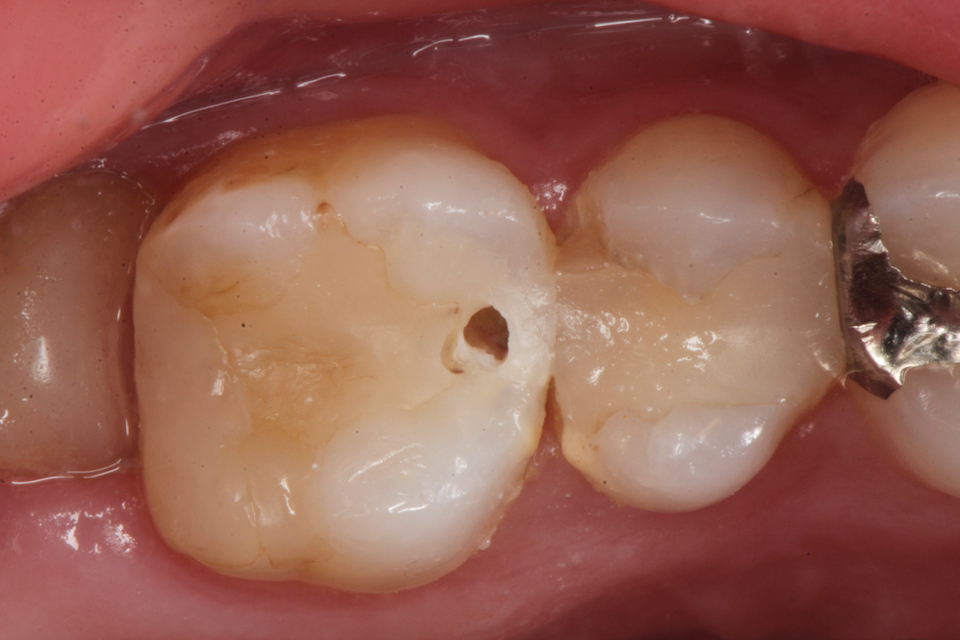

下顎7番の頬側歯茎部カリエスの原因 2025.06.04